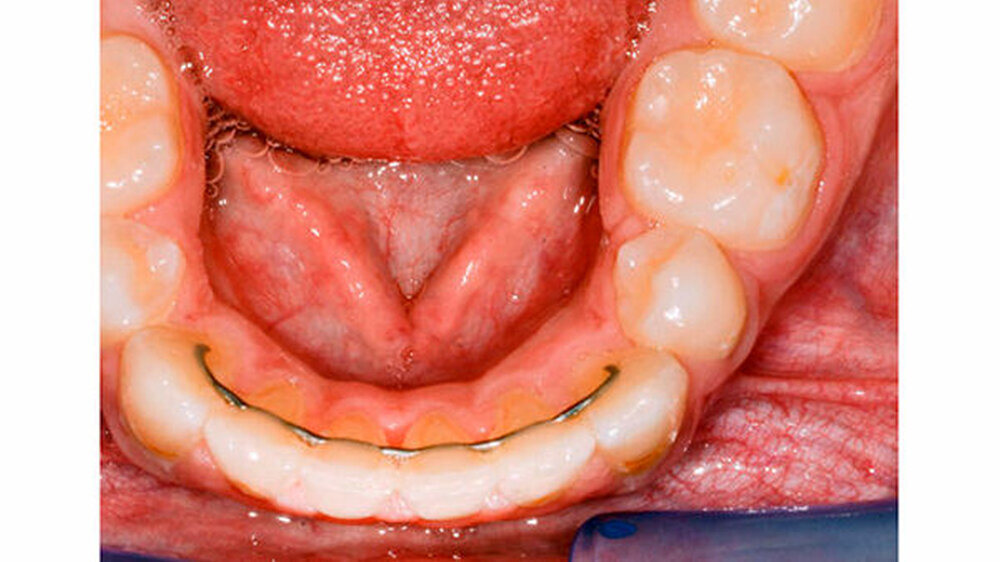

Der extraorale Befund zeigte eine normale Sensibilität der Unterlippe. Intraoral am Alveolarfortsatz des linken Unterkiefers regio 32-34 lingual konnte eine circa 2×2,5 cm große, schmerzreie knöcherne Vorwölbung palpiert werden (Abbildung 1). Die Zähne 31-36 reagierten normal auf den Test mit CO2-Schnee.